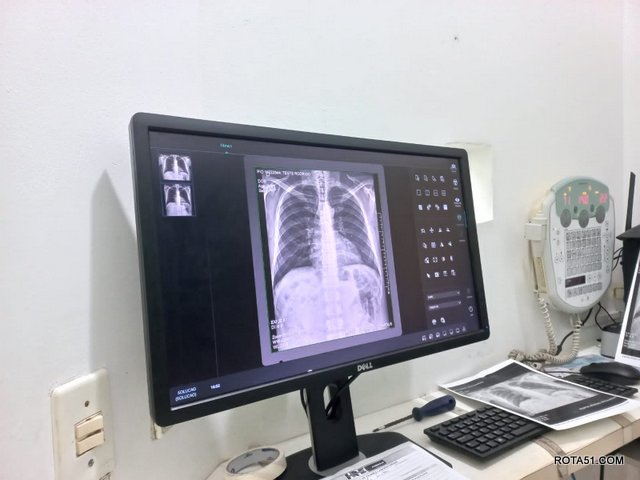

Com a retomada da gestão do Hospital Regional de Eunápolis (HRE), a Prefeitura de Eunápolis está dedicando esforços significativos para aprimorar os serviços de saúde oferecidos à comunidade. Uma das últimas iniciativas mais recentes envolveu a instalação de um equipamento de Raio-X de última geração no setor de Radiologia do HRE.

Essa tecnologia de ponta não apenas proporciona laudos mais precisos, mas também aumenta a capacidade do hospital para realizar exames, pois as imagens aparecem instantaneamente no monitor, agilizando o diagnóstico e tratamento dos pacientes. Com a introdução do equipamento, a unidade agora tem a capacidade de realizar o dobro de exames, beneficiando diretamente a comunidade local.